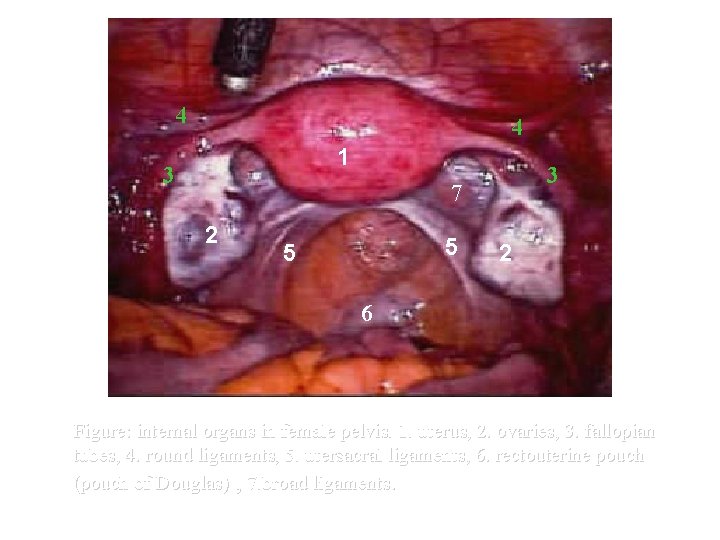

4 4 1 3 3 7 2 5 5 2 6 Figure: internal organs in female pelvis. 1. uterus, 2. ovaries, 3. fallopian tubes, 4. round ligaments, 5. utersacral ligaments, 6. rectouterine pouch (pouch of Douglas) , 7. broad ligaments.